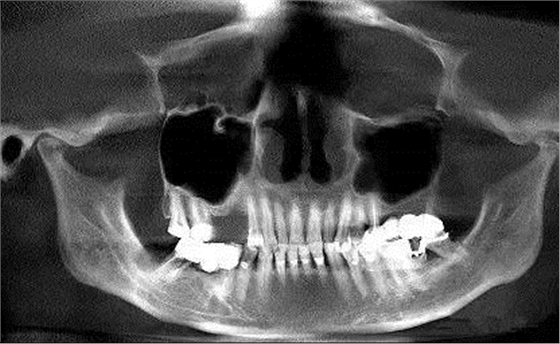

第三圖:上頜竇氣化導(dǎo)致上頜竇過大,上頜竇底骨質(zhì)向紙張一樣薄。只適合做外提升。